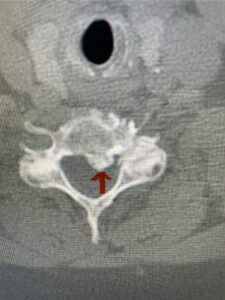

In this next case, this patient is a 47 year-old female who presents with intractable low back pain with severe pain, numbness, and weakness in the right lower extremity that had gotten progressively worse over a year. The patient had failed conservative management including physical therapy and epidurals. She was noted to have ⅘ weakness of plantar flexion. MRI demonstrated a large right L5-S1 disc herniation with severe compression of the descending right S1 nerve root (Fig 3). It was decided to perform a right L5-S1 hemilaminectomy for removal of the disc fragment and decompress the S1 nerve root. When you expose the disc, one must be certain to release any anterior adhesions to the nerve root in order to prevent a dural tear during retraction of the nerve root. It is also important to make sure during exposure and you finally encounter the dura after removing the ligamentum and fat, to make sure you are looking at the nerve root and not the main trunk of the thecal sac because if you don’t you can avulse or damage the nerve root if you retract the wrong structure.

Fig. 3a: Sagittal and axial T2-weighted lumbar MRI images demonstrating large right L5-S1 disc herniation (red arrows)

We found a massive subligamentous herniation which had to be revealed by having your partner retract the freed nerve root with a nerve root retractor and putting slight downward pressure on the more medial and anterior disc space. There is nothing more satisfying when the jelly (disc fragment) of the annulus (donut) comes squirting out and you remove a large chunk of disc material that clearly was stretching the ligament membrane and compressing the nerve root. This does cause back pain in addition to radiculopathy not only by the component of mechanical compression but also the stretching of the nerves within the ligament. We performed this surgery and noted that the nerve root was a very angry red color or hyperemic and we removed a large subligamentous fragment. The patient had improvement of her preoperative radicular symptoms.